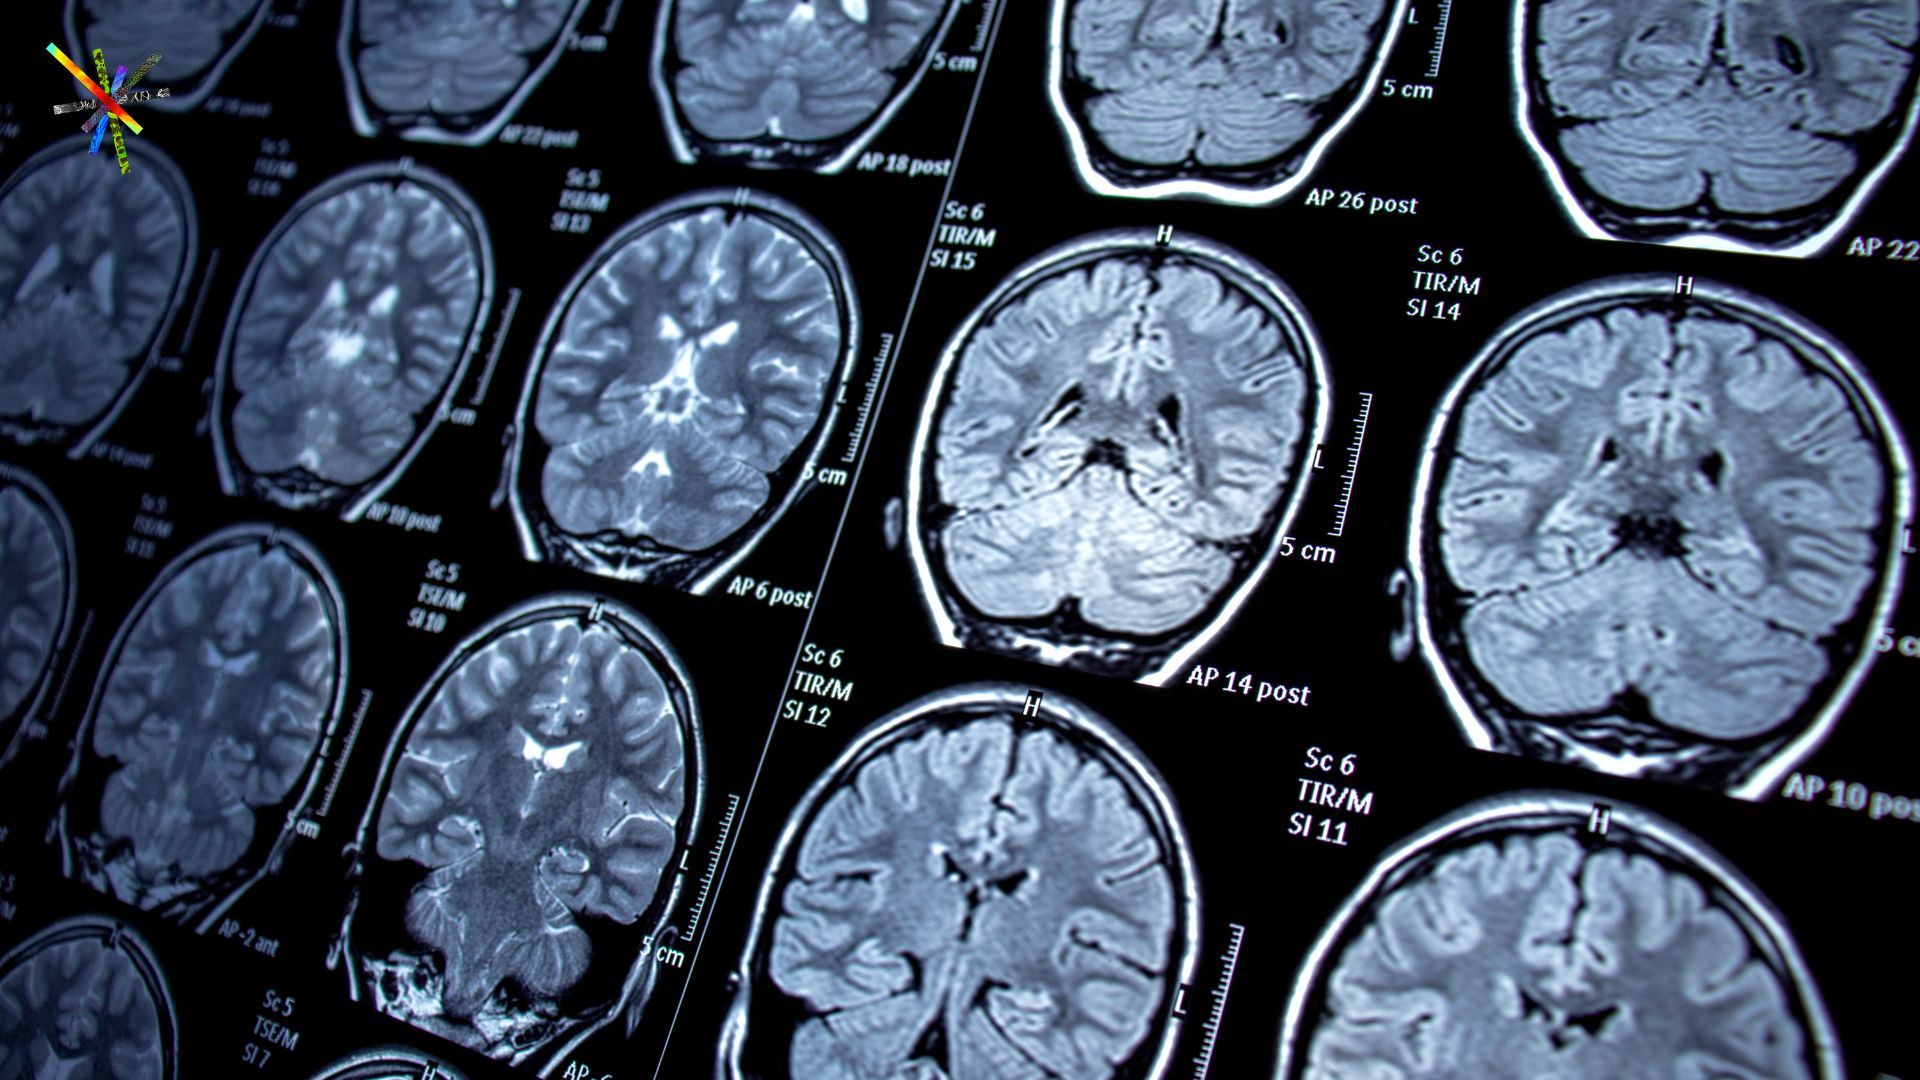

Researchers at the Martinos Center are advancing MRI acquisition technologies to map human brain structure and function with significantly enhanced capability—delivering high image fidelity, richer information content, and unprecedented spatial resolution (from standard to mesoscopic scale). Through the development of Echo Planar Time-resolved Imaging (EPTI)—a next-generation MRI acquisition that introduces novel data encoding and image formation methods to overcome major limitations of conventional methods—Fuyixue Wang, Zijing Dong and colleagues have demonstrated major gains in sensitivity and specificity for probing human brain organization.